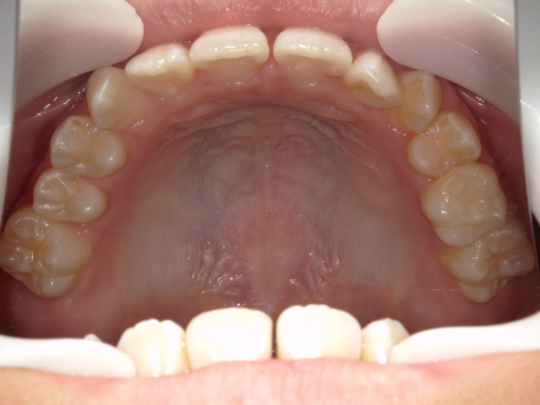

治療前

治療説明

歯科矯正で取り外し可能な矯正方法である床矯正とチンキャップで治療しました

治療期間 4年6か月

治療費用300000 円

治療後

治療の副作用(リスク)歯の動き方には個人差があり、予想された治療期間が延長する可能性があります。。床矯正の使用状況、矯正歯科治療には患者さんの協力が必要であり、それらが治療結果や治療期間に影響します。2次矯正が必要になる場合もあります。